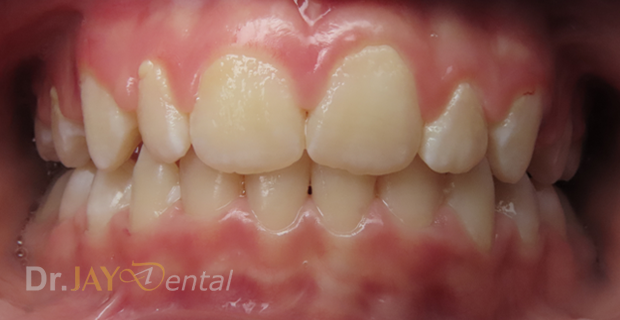

CASE 8

Patient had open bite and severe mouth breathing . At our office , patient went through myofunctional therapy , expansion of upper and lower jaw and aligning of teeth . No extractions needed and orthodontics was focused on airway, correcting habits and giving importance to the holistic health of patient. Patient’s mom extremely happy with the result.

Before

After